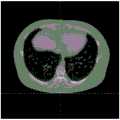

FIG. 3 is a schematic view of the location of the xiphoid process in a horizontal slice;

2.3, in the current slice, finding foreground pixels (1) located around the midsagittal plane (MSP) and having the lowest i-coordinate; if the slice is found, the next level slice (k is k-1) is selected to continue searching; if not found, the selection is finished; the i-coordinate represents the horizontal line in the graph, and the lowest i-coordinate is the lowest line of the CT section of the human body with effective image pixels, as shown in FIG. 1.